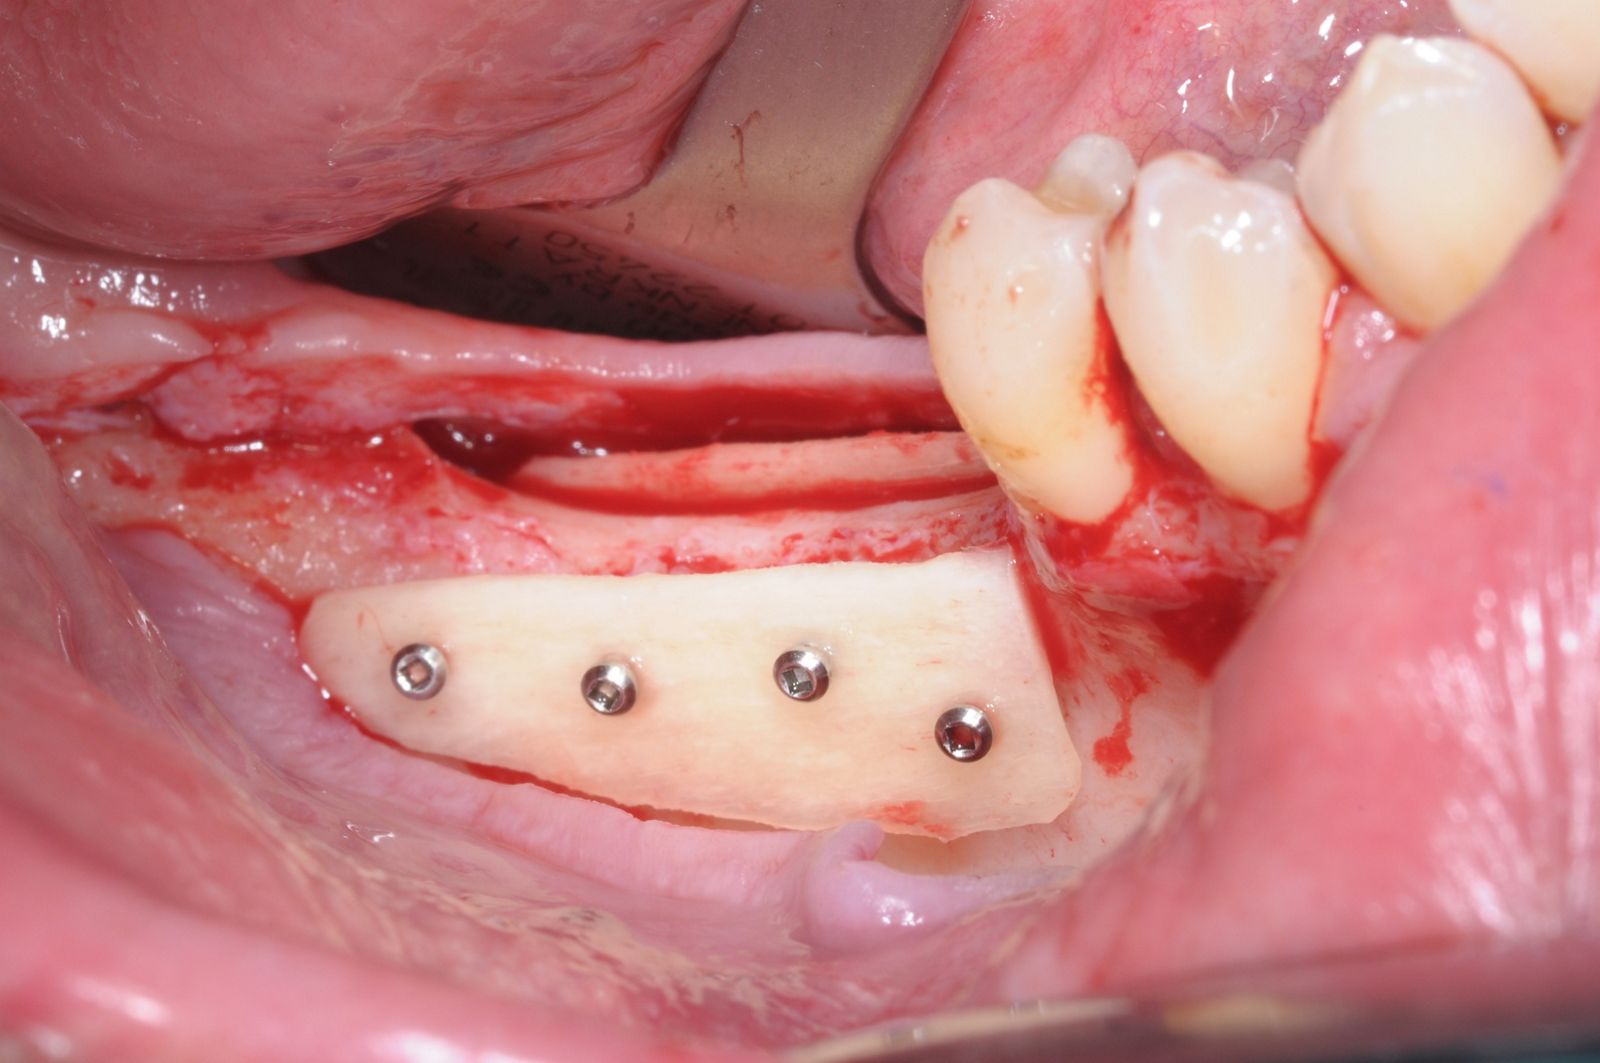

07/28 - Occlusal view on the immobile container created with the two cortical platesThree-dimensional augmentation with maxgraft® cortico - Dr. R. Würdinger